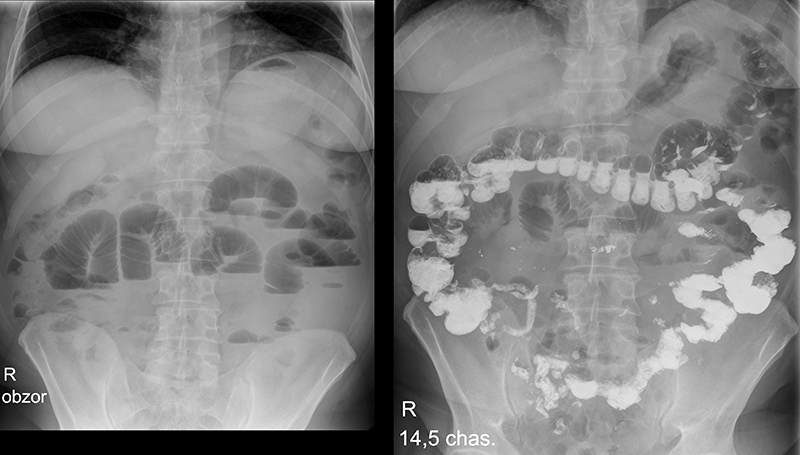

Рентгеноконтрастные Исследования Кишечника: Визуализация и Методики